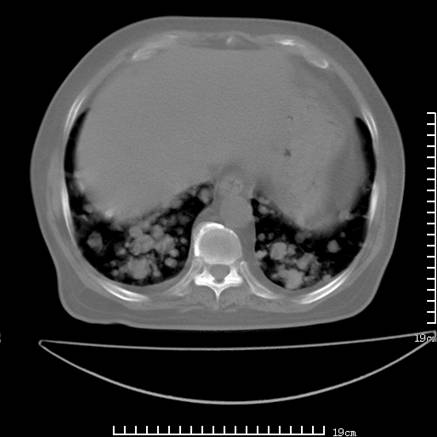

张男,75岁,干咳半年余,小便不利二年,b超检查前列腺增大,未见明显肿块;前列腺癌血生化检查多项指标明显增高。

双肺内多发转移瘤,纵膈淋巴结转移。来源前列腺?建议盆腔mri进一步检查。

双肺转移满了。

两肺广泛转移瘤。